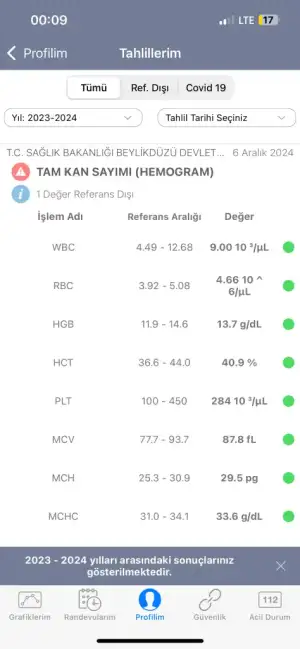

Merhaba bugün kadın hastalıkları ve doğum bölümüne gittim rahim ağzında yara var diye ve bana yakma önerdiler bi kaç test yaptılar anestezi için ve sonuçları pazartesi göstericem ama sonuçlar çıktığı için merak ediyorum aranızda anlayan veya doktor olan biri varsa cevaplayabilirmi rica etsem?

IMG_8035.webp32,3 KB · Görüntüleme: 115

IMG_8035.webp32,3 KB · Görüntüleme: 115 -

IMG_8036.webp32,2 KB · Görüntüleme: 112

IMG_8036.webp32,2 KB · Görüntüleme: 112 -

IMG_8037.webp20,9 KB · Görüntüleme: 115

IMG_8037.webp20,9 KB · Görüntüleme: 115 -

IMG_8038.webp21,8 KB · Görüntüleme: 104

IMG_8038.webp21,8 KB · Görüntüleme: 104 -

IMG_8039.webp21,3 KB · Görüntüleme: 108

IMG_8039.webp21,3 KB · Görüntüleme: 108 -

IMG_8040.webp18 KB · Görüntüleme: 105

IMG_8040.webp18 KB · Görüntüleme: 105 -

IMG_8041.webp20,9 KB · Görüntüleme: 101

IMG_8041.webp20,9 KB · Görüntüleme: 101 -

IMG_8042.webp40,6 KB · Görüntüleme: 115

IMG_8042.webp40,6 KB · Görüntüleme: 115